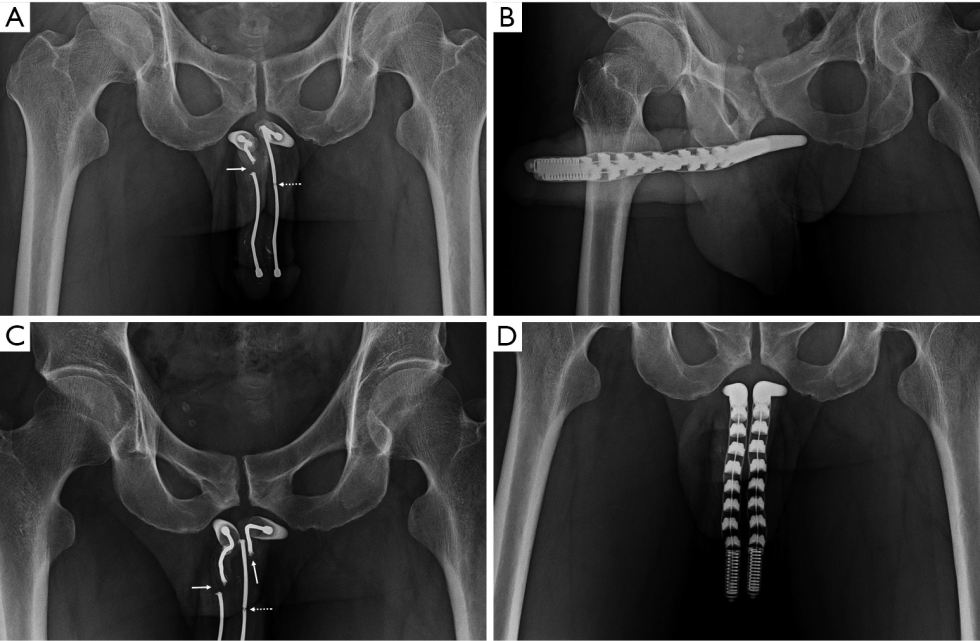

Falloprosthesis: Coloplast Titan OTR, AMS 700 CX, AMS 700 LGX